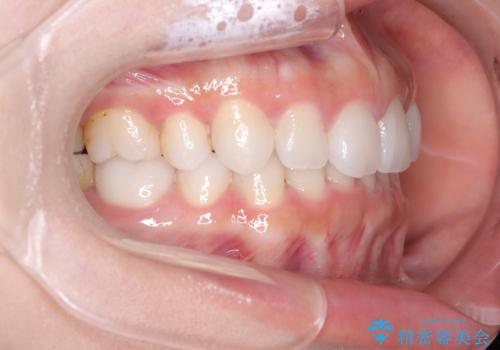

- 上下の歯の中心(正中)のズレと、口元の見た目を気にされて来院されました。精密な検査の結果、咬み合わせのバランスを整えながら、正中線を一致させる治療が必要と判断。患者様のご希望に合わせ、透明で目立ちにくいインビザライン(マウスピース矯正)による治療計画を立案しました。歯列全体を奥(遠心)へ移動させるためにゴムかけを併用。さらに、見た目を改善するため、既存の金属の被せ物をセラミッククラウンに交換することも治療計画に組み込みました。

今回の矯正治療では、透明なマウスピース型の装置インビザラインを使用しました。歯列を奥へ動かす遠心移動の効率を高めるため、患者様ご自身にゴムかけも行っていただきました。この併用によって、歯をより正確かつスムーズに動かすことができ、上下の歯の中心である正中線を一致させることが可能になりました。また、治療の最終段階では、以前から入っていた金属の被せ物を、天然歯に近い色合いのセラミッククラウンに交換。矯正治療と審美治療を組み合わせることで、機能的な咬み合わせの改善に加え、金属が見えない、より自然で美しい口元を獲得していただけました。